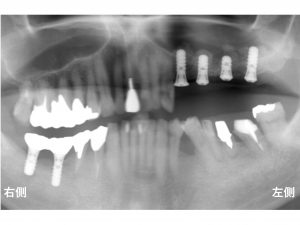

以下が下顎右側のインプラント手術後です。

以下がインプラント手術が終わった直後です。

そして、

以下が治療が完了した後です。

このように様々な治療法を併用しながらインプラント治療は行われるのです。